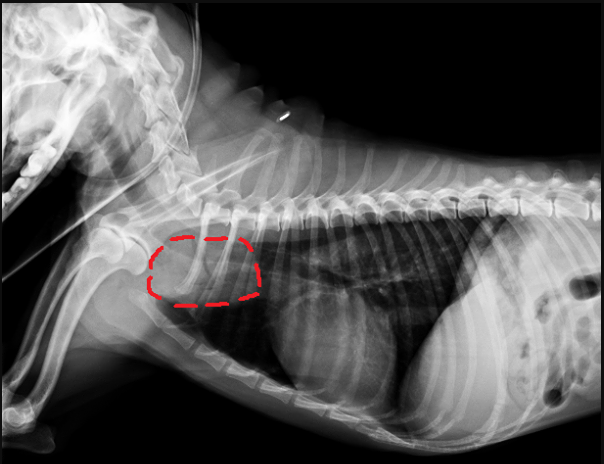

門診X光片的結果,在心臟的頭側、與前縱膈重疊處發現了不透明度上升、且含有不規則空氣線條的異常影像(圖一)

圖一